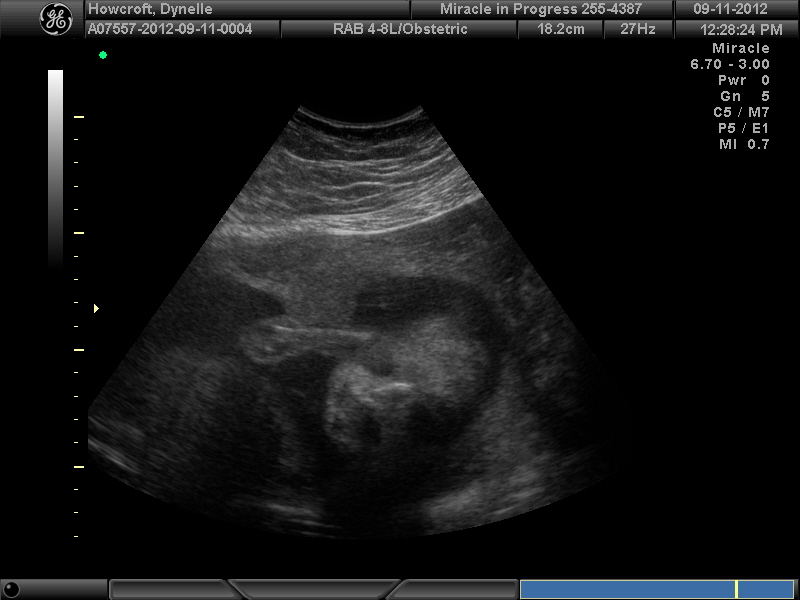

We were lucky to get a free 3D ultrasound of our little guy at 26 1/2 weeks. He was so not cooperative and had his hands and feet in his face the entire time. We weren't shocked he seems to be a little on the shy side. It was so fun to see him moving around and we even got to see him swallowing. Pregnancy is absolutely amazing I tell you. Isn't he just so handsome? I can't wait to introduce you to him!